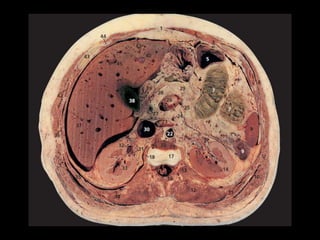

Órgão exócrino e endócrino

Mede aproximadamente 15 cm de comprimento

Relação anatômica com estômago, duodeno, cólon

e baço

São possíveis variações consideráveis no tamanho,

forma e localização

Situa-se no espaço pararrenal anterior do

retroperitônio

Divide-se em cabeça, processo uncinado, colo,

corpo e cauda